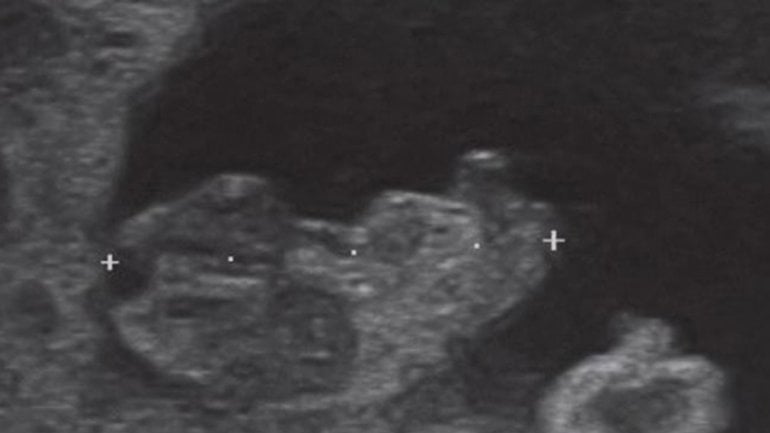

Ultraschall 14. SSW

Auf diesem Bild sieht man eine Zwillingsschwangerschaft mit zwei Fruchtblasen. Die meisten Zwillinge, ob eineiig oder zweieiig, haben eine eigene Fruchtblase und eine eigene Plazenta. Selten teilt sich die befruchtete Eizelle bei eineiigen Zwillingen erst spät in der Entwicklung in zwei Embryos auf, was zu einer gemeinsamen Fruchtblase und Plazenta führt. Ab dieser Woche kann man mit etwas Glück das Geschlecht des Babys erkennen.